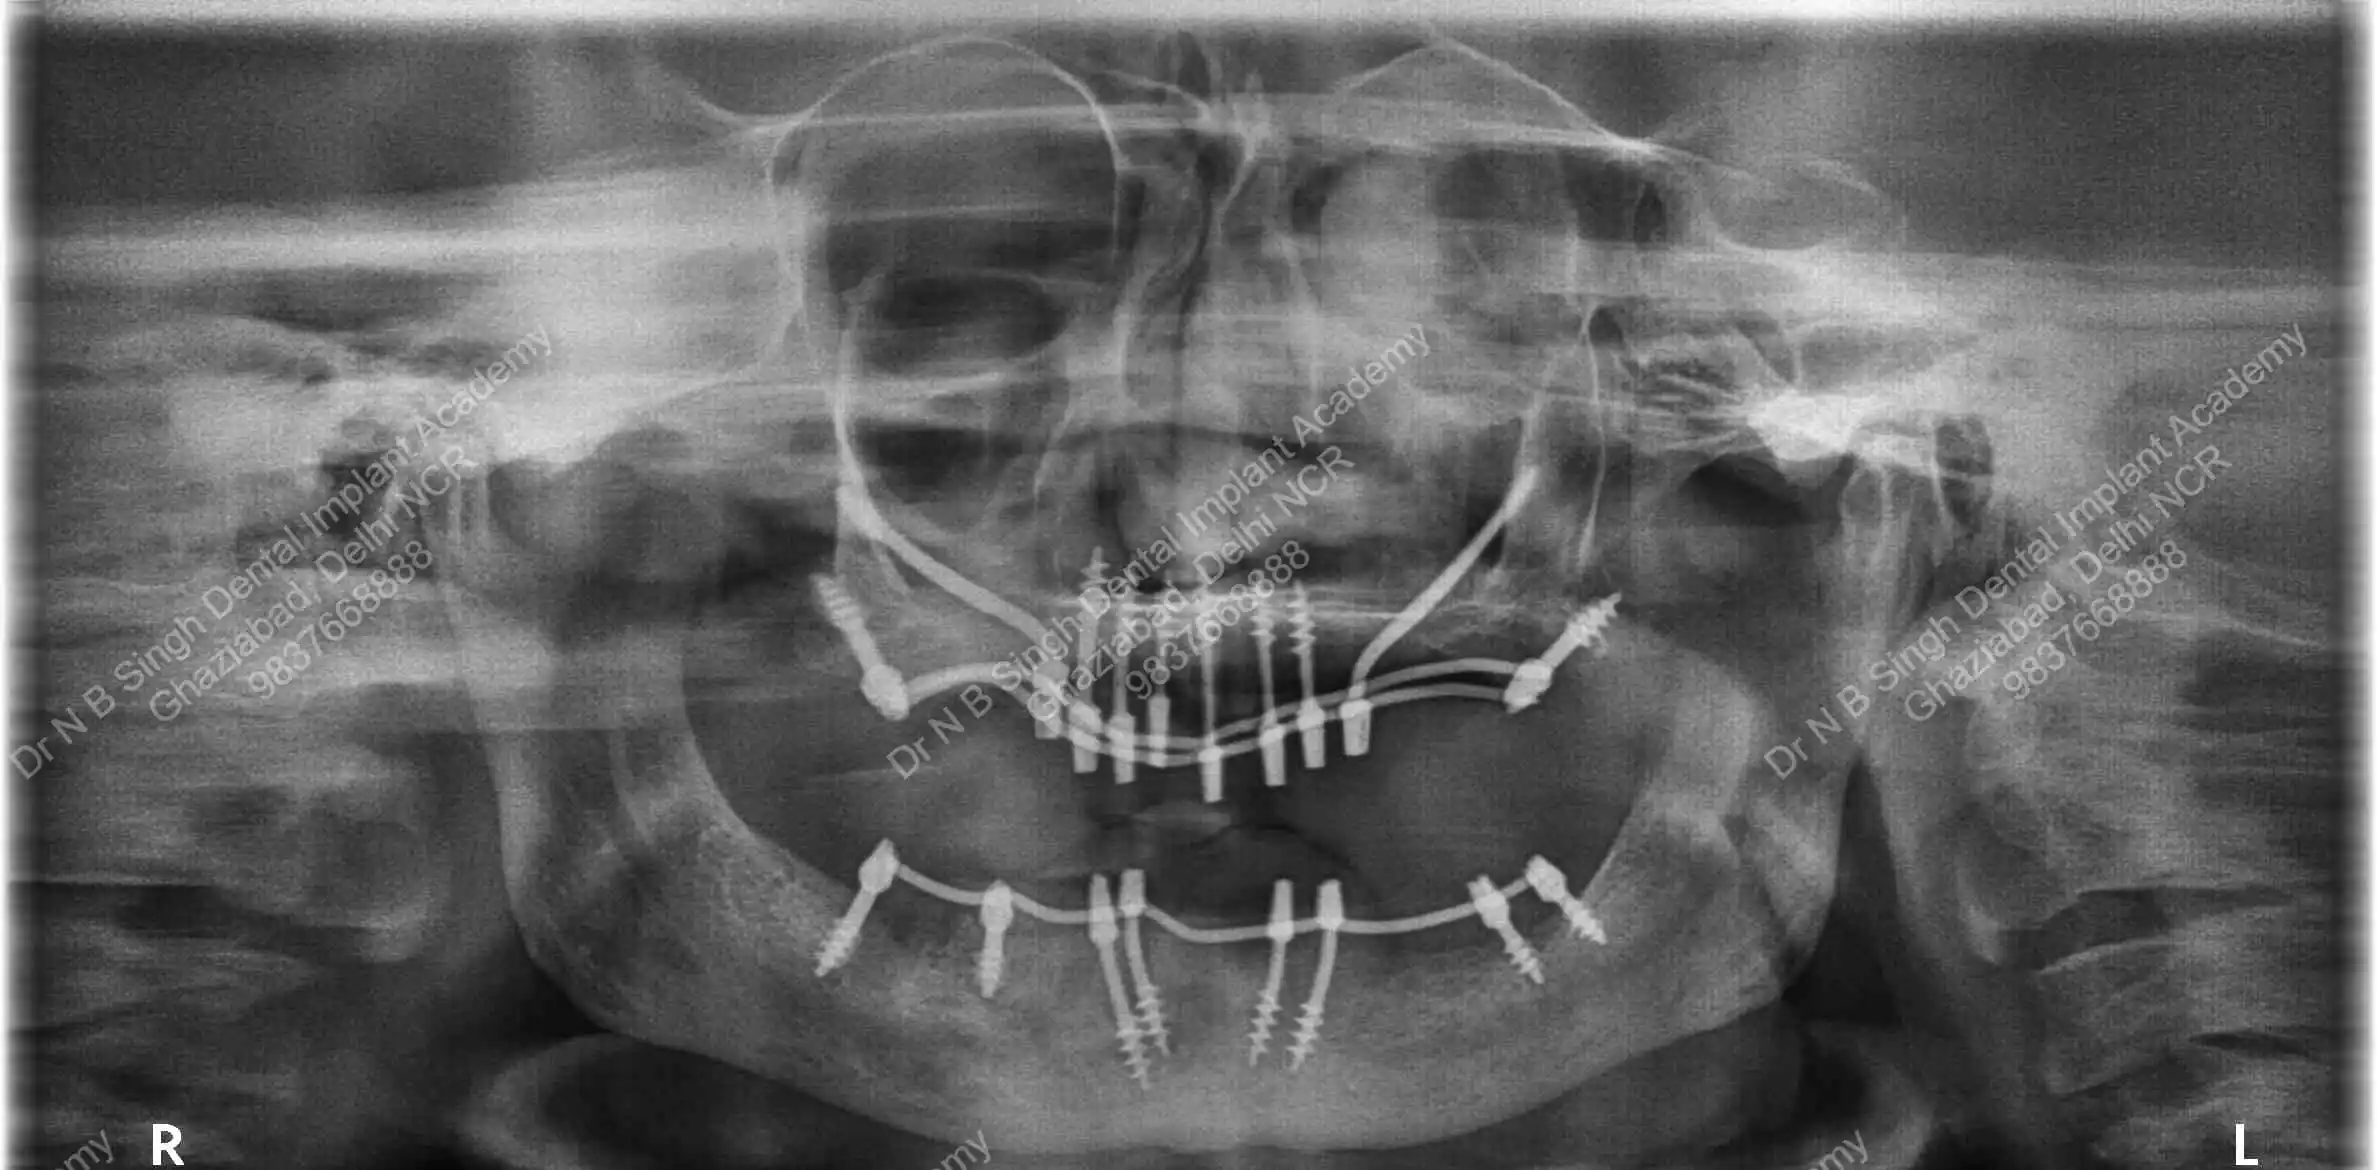

A008 Basal implants – af-qurs 1

Dr. N.B. Singh